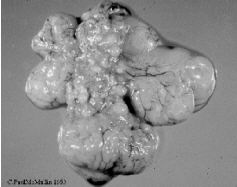

- Follicles flaccid.

| Figure 22. Flaccid ovarian follicles in a broiler parent chicken undergoing challenge with Infectious Bronchitis virus. |